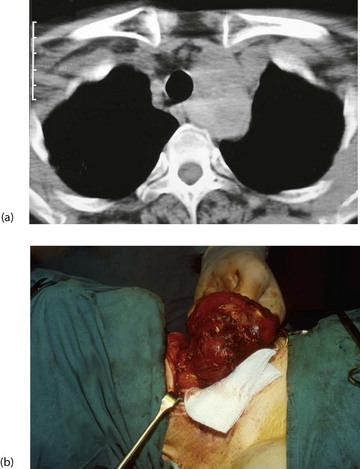

Ultrasound scanning is useful to establish morphology and diagnose cysts. It can also indicate retrosternal extension. CT scans of neck and thoracic outlet are taken if malignancy is suspected or if there appears to be tracheal displacement or compression (Figs 49.6).

Fig. 49.8 Thyroid and parathyroid operations

(a) The drawings show the standard neck exploration approach to thyroid and parathyroid operations, and the structures at particular danger—the recurrent laryngeal nerve and parathyroid glands. In the photographs, (b) shows neck exploration for hyperparathyroidism. A collar incision has been made and upper and lower flaps are held apart with the specially designed Joll's retractor. A single large parathyroid adenoma is clearly visible. (c) Subtotal thyroidectomy specimen after operation for hyperthyroidism. (d) Total thyroidectomy specimen after operation for right-sided medullary carcinoma. Involved lymph nodes were ‘cherry picked’ and are also shown